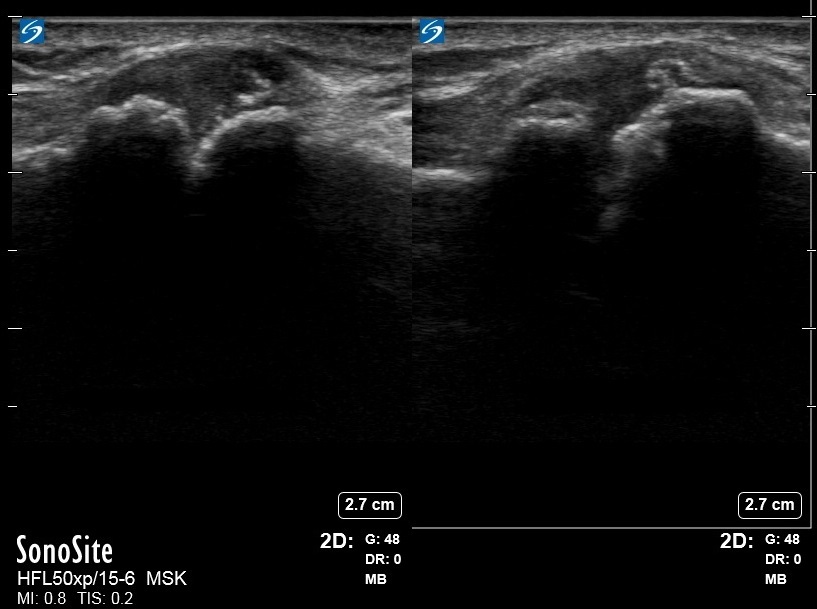

Imagen dinámica de la articulación AAC osteoartrítica del hombro

Izquierda: Compresión

Derecha: Neutro